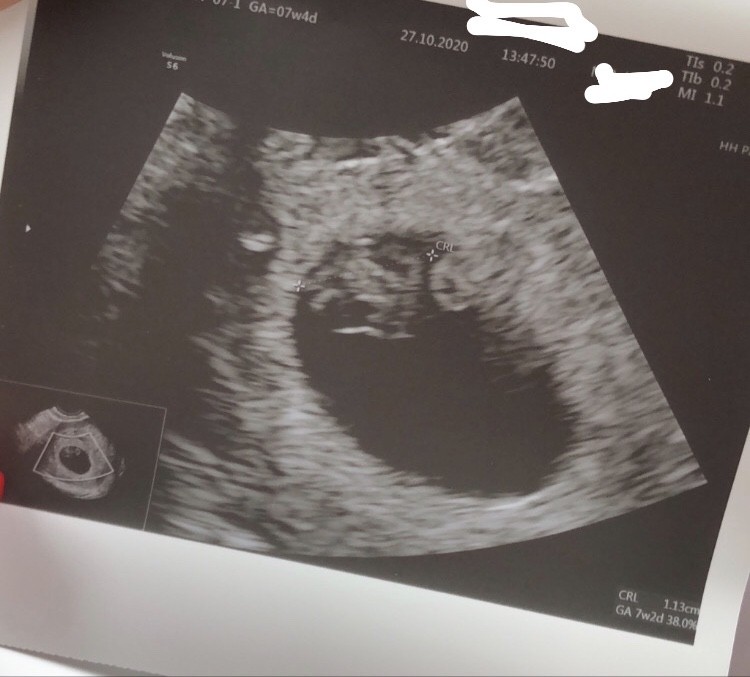

Jestem po wizycie ❤ Serduszko bije, dzidziuś ma ponad 1cm . Lekarz śmiał się ze mam tak pięknego dzidziusia że sam by takiego chciał 😃 założył kartę ciąży, dał skierowanie na badania wszystkie i na badania prenatalne. Cieszę się ze wszystko na NFZ. Kupiłam globulki bo jakaś infekcja się pojawiła , przy pobieraniu cytologii zauważył. Kupiłam tez Suplementy dla kobiet w ciąży. Kontrola za 2tyg, przedłużył zwolnienie na razie 2tyg a później już na dłużej. Sam powiedział ze po co chodzić teraz do pracy i się narażać. Zanim zaczęłam prace w tej placówce w której razem pracujemy tez był taki miły i to dla każdej pacjentki. Wiec czasami zdarzy się super gin na NFZ. Nie traćmy nadziei ☺